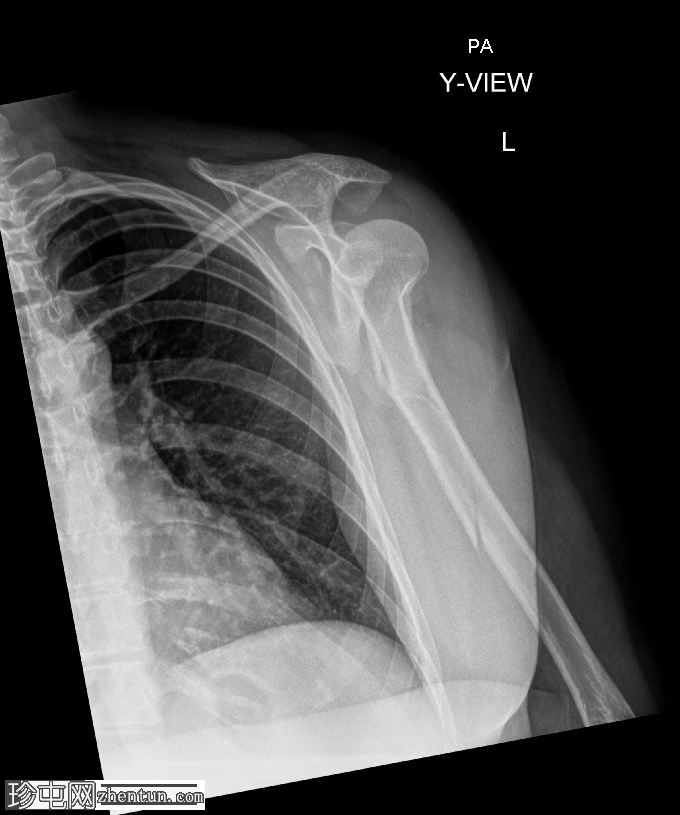

正位

肱骨近端粉碎性移位骨折,累及骨干近端半部、外科颈,并延伸至大结节。

肱骨头在肩关节内向下半脱位,肩峰肱骨间距增大。

肱骨头向下移位(假性半脱位)是肱骨近端骨折常见的继发性表现。它提示关节积液、关节积血或暂时性关节囊松弛,而非肩关节真正的不稳。手臂负重和肌肉张力下降(尤其是三角肌和肩袖肌群)共同导致肱骨头相对于肩胛盂位置下移<sup>1-3</sup>。

这种表现不应与真正的肩关节脱位混淆,因为在Y形位或轴位影像上,肱骨头仍与肩胛盂保持正确的对位。随着关节液的吸收和肌肉张力的恢复,这种情况通常会自行缓解。识别这种暂时性的良性表现对于避免不必要的复位手术至关重要。

在本病例中,肱骨头位置下移反映了由急性近端肱骨骨折引起的关节积液所致的假性半脱位,而没有真正的脱位证据。